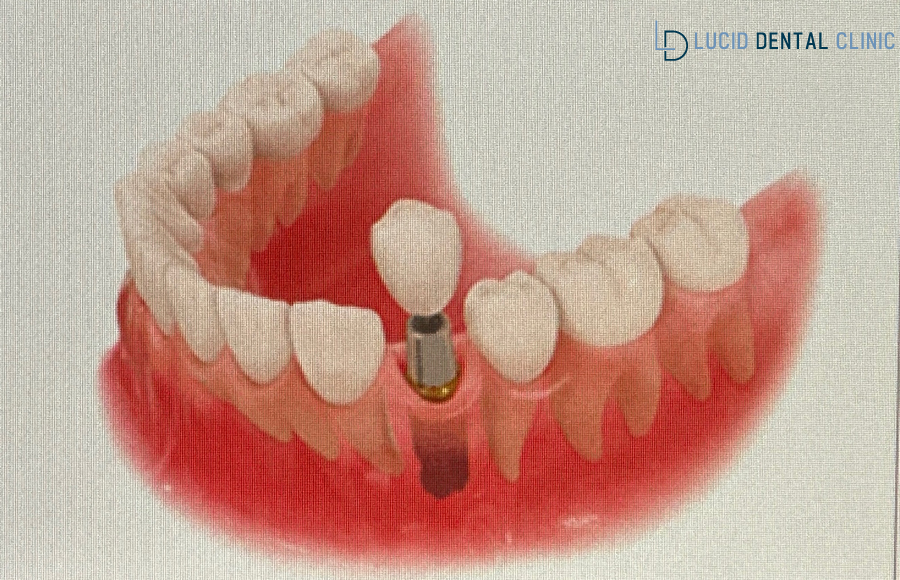

언주역 치과 는 곧바로

조금 더 안전하고 정밀한

식립이 이뤄질 수 있도록

계획 수립에 들어갔는데요.

따라서 언주역 치과 에서 시행하는

3D 디지털 분석 프로그램으로

미리 모의 식립을 진행하여

가이드를 만들기로 했는데요.

이 디지털 분석 프로그램 가이드를 이용하면

계획된 위치에 픽스처를 즉시 식립할 수 있습니다.

또한 즉시 식립과 최소한의 절개로 진행되기 때문에

부기와 통증이 덜하다는 장점을 가지고 있는데요..